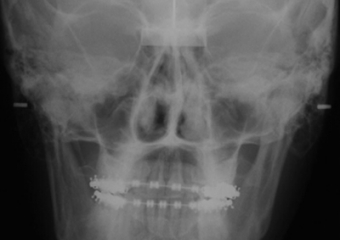

Telerradiografia frontal após cirurgia